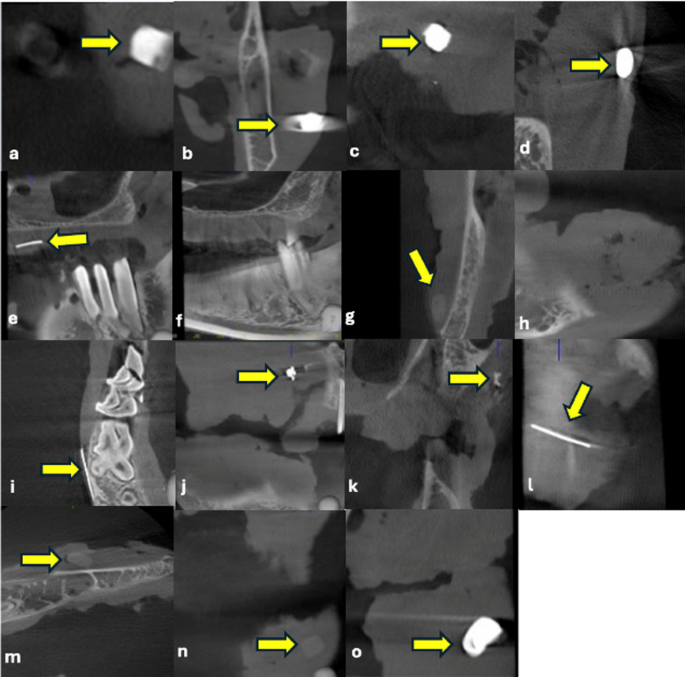

CBCT imaging of DMs; (a) Composite, (b) Amalgam, (c) Glass-ionomer cement, (d) Zincopolycarboxylate cement, (e) Gutta percha, (f) Paper point (not visible), (g) Acrylic, (h) Wax (not visible), (i) Needle, (j) Stainless steel bracket, (k) Ceramic bracket, (l) Ni-Ti wires, (m) Alginate, (n) Acrylic tooth, and (o) Metal ceramic crown.

Table 4 presents detailed information on the CBCT visibility and radiopacity, as well as USG visibility, echogenicity, and artifact presence for each DM. In CBCT, paper point and wax were not visible, whereas all materials were detected with USG. In CBCT, acrylic, ceramic bracket, alginate, and acrylic tooth were classified as “slightly opaque.” In USG, most materials appeared hyperechoic, with alginate being the only material identified as isoechoic. Artifact patterns varied depending on the material, with posterior acoustic shadowing and comet-tail artifacts being the most frequently observed. This table clearly shows the differences in performance and imaging characteristics between the two modalities based on material type (Figs. 2 and 3).

The detection performance of imaging modalities depends on the physical principles underlying the technology used. In CBCT, visibility is determined by a material’s ability to attenuate X-rays, known as radiopacity, and the difference in density between the material and the surrounding tissue. Due to their high X-ray attenuation, materials containing metal (e.g., amalgam, metal-ceramic crowns, and Ni-Ti wires) are clearly visualized. In contrast, low-density organic materials, such as paper point and wax, were not detectable on CBCT due to their low X-ray absorption. Visibility in USG depends on the difference in acoustic impedance between the material and the surrounding tissue. A high impedance mismatch results in a strong reflection of ultrasound waves, producing a hyperechoic appearance6,9,10,16. In our study, most materials appeared hyperechoic, whereas alginate, which has a density close to water, was evaluated as isoechoic. This can be attributed to the acoustic properties of alginate being similar to those of the surrounding soft tissue.

Artifacts can significantly impact the diagnostic accuracy of imaging methods. In CBCT, the most common artifacts are beam hardening, streaking, and scattering. High-density metal-containing materials (e.g., amalgam, metal-ceramic crowns, and Ni-Ti wires) strongly attenuate X-rays. This causes beam hardening, resulting in gray tone loss, reduced contrast, and masking of surrounding details. Streak artifacts are often seen around thin metallic structures and may obscure low-density or small foreign bodies within the shadow of metal artifacts. This can lead to false negatives. In USG, artifacts such as posterior acoustic shadowing and comet-tail patterns can assist in detecting foreign bodies, but they can also mislead interpretation. Shadowing is pronounced in materials with high acoustic impedance differences, while the comet-tail artifacts are typically observed around metallic materials. However, these findings may be faint or absent in small or low-reflectivity objects, and normal structures, such as calcifications or fibrotic tissue, can mimic them. Furthermore, prior surgical intervention may cause air to accumulate within the tissue, which complicates the imaging process and can result in erroneous findings. Accurate interpretation requires considering the physical properties of the material, the surrounding tissue, and the device settings. MAR algorithms in CBCT and multiplanar probe positioning in USG can improve diagnostic accuracy5,9,12,14,16,17.